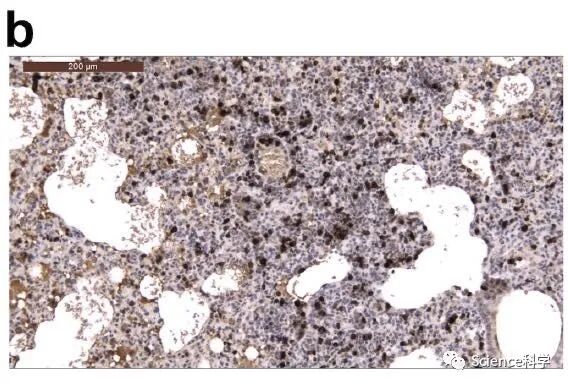

在接种病毒后2天和5天检测到病毒抗原的区域,可以观察到单核细胞浸润。SARS-CoV-2的N蛋白的免疫组织化学表明,在接种病毒后2天,金仓鼠的支气管上皮细胞中存在病毒抗原(下图的箭头所指位置)。

在接种病毒后5天,其发展为肺细胞(下图的箭头所指位置)。